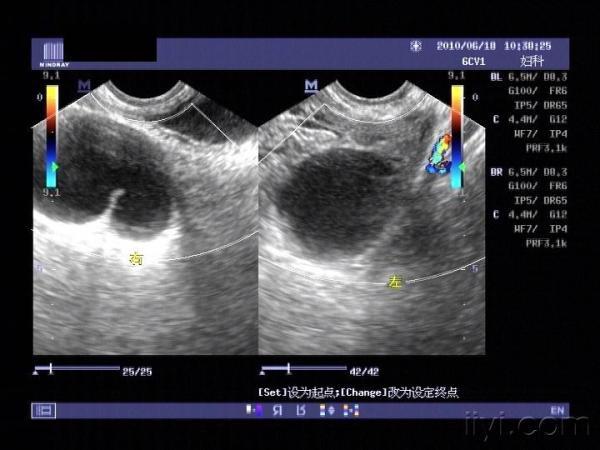

大家来帮我看看,右边这个是输卵管积水还是卵巢囊肿?

右侧附件区和左侧附件区各见一囊性包块

在双侧卵巢清晰显示的情况下,附件区囊状光团,尤其是呈肠管形时,输卵管积液可能极大。